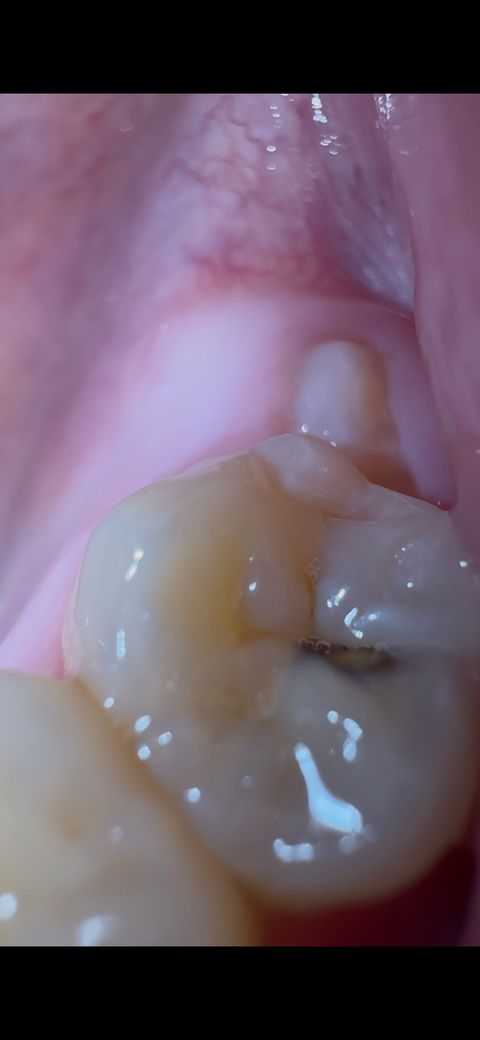

치아(어금니)에 충치가 좀 크게 생긴 것 같아요

어느날 밥을 먹다가 위쪽 그리고 오른쪽 어금니가 깨지는 느낌이 났어요

그러니까 어금니 외곽쪽이 깨진 것 같아보이네요

사랑니 나기 전 가장 바깥 어금니에요

누가봐도 심각할 정도의 충치가 있더라구요

지금 사진만 봐선

어느정도 단계의 충치인지도 모르겠고

사진만으로 견적을 내기는 어렵지만 단순한 충치일 경우에는 10만원대, 신경치료가 필요하면 수십만원 필요합니다

사진상 봐서 충치가 어느 단계인지 알 수 있는 치과의사는 없습니다. 엑스레이를 찍어봐야 합니다. 다만 증상을 봐서는 신경치료가 필요한 단계는 아닌 것 같고 충치 제거 후 레진 수복 시도합니다. 레진수복 비용은 10만원 내외 입니다.

사진만으로는 어떤치료를 해야될지 판단하기 어렵고 엑스레이 사진을 찍어보셔야될것같습니다. 충치가 상당히 깊어 보입니다.

사진으로 봤을 경우에는 내부까지 크게 진행되는 것 같은 모습을 보이긴 합니다. 정확한 충치의 범위를 알기 위해서는 엑스레이 사진이 필요하며 충치를 직접 제거해봐야 알 수 있습니다. 충치를 제거했을 경우 신경까지 충치가 진행되어 있다면 신경 치료 후 크라운 치료가 필요할 수도 있습니다.